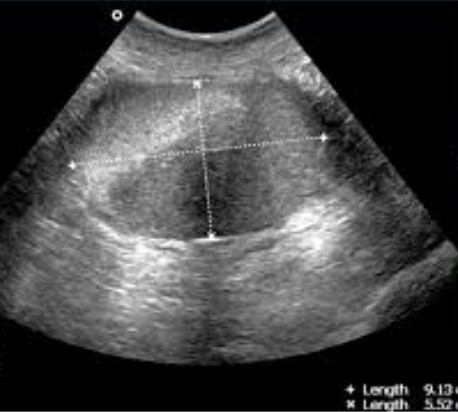

МРТ или УЗИ малого тазаНа этот вопрос однозначный ответ также должен давать лечащий врач. Однако отметим, что УЗИ является более доступным  и дешевым методом, не имеет никаких противопоказаний (может выполняться при наличии кардистимулятора, ферромагнитных предметов в теле, клаустрофобии и пр). С помощью УЗИ оценивают анатомическое состояние тазовых органов и определяют патологические образования, при этом совсем незначительные очаги могут быть не визуализированы. Однако для окончательных выводов о природе процесса, его возможной злокачественности, оценки размеров, степени развития патологии требуется уточнение методом МРТ, которая характеризуется большей информативностью и достоверностью.